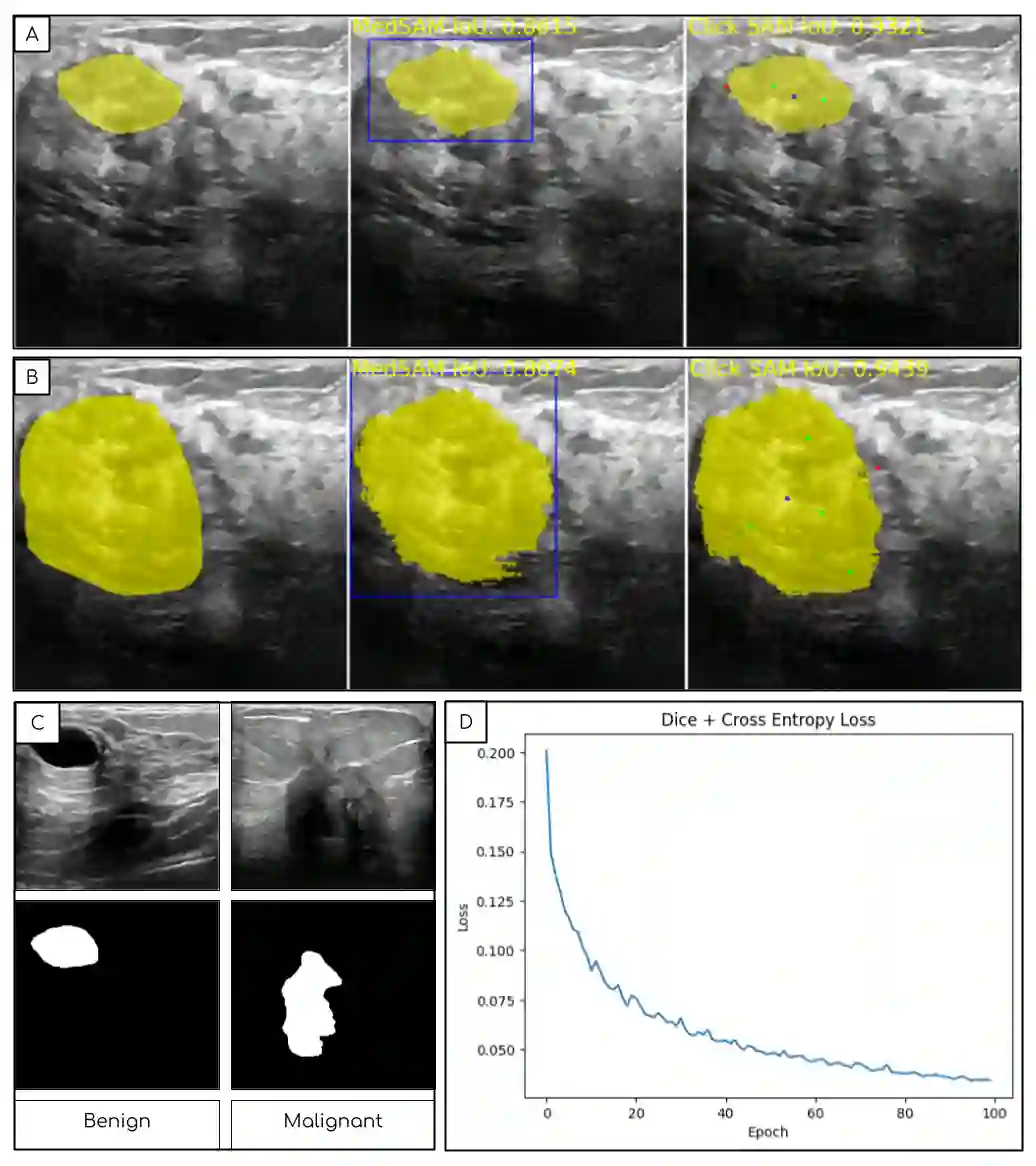

The newly released Segment Anything Model (SAM) is a popular tool used in image processing due to its superior segmentation accuracy, variety of input prompts, training capabilities, and efficient model design. However, its current model is trained on a diverse dataset not tailored to medical images, particularly ultrasound images. Ultrasound images tend to have a lot of noise, making it difficult to segment out important structures. In this project, we developed ClickSAM, which fine-tunes the Segment Anything Model using click prompts for ultrasound images. ClickSAM has two stages of training: the first stage is trained on single-click prompts centered in the ground-truth contours, and the second stage focuses on improving the model performance through additional positive and negative click prompts. By comparing the first stage predictions to the ground-truth masks, true positive, false positive, and false negative segments are calculated. Positive clicks are generated using the true positive and false negative segments, and negative clicks are generated using the false positive segments. The Centroidal Voronoi Tessellation algorithm is then employed to collect positive and negative click prompts in each segment that are used to enhance the model performance during the second stage of training. With click-train methods, ClickSAM exhibits superior performance compared to other existing models for ultrasound image segmentation.